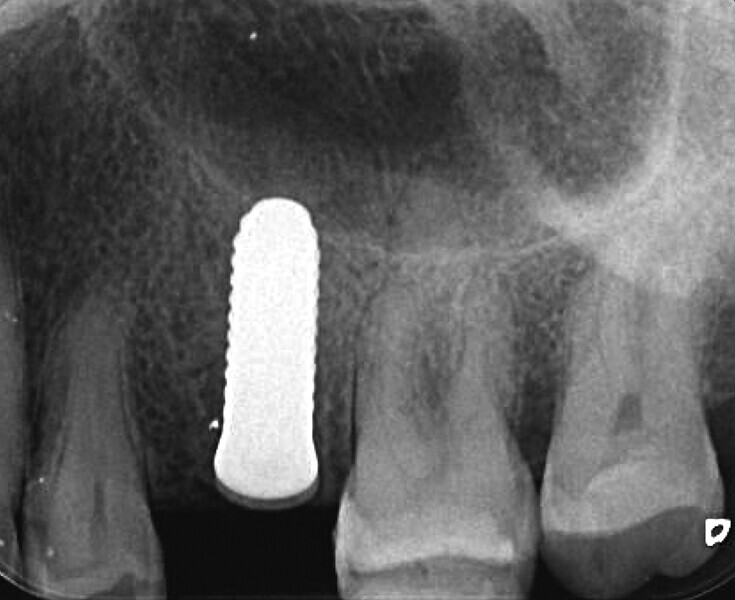

Fig. 44 : Radiographie de contrôle et excellente intégration de l’implant en céramique dans l’environnement parodontal.

Fig. 45 : Radiographie de contrôle et excellente intégration de l’implant en céramique dans l’environnement parodontal.

Un patient présentant un défaut infraosseux s’est présenté au cabinet dentaire avec le souhait explicite d’un traitement par un implant en zircone, pour remplacer l’une de ses molaires. Un implant deux pièces en zircone a donc été posé et le défaut infra-osseux a été traité dans le même temps, au moyen d’une allogreffe osseuse et du dérivé de matrice amélaire Emdogain (Straumann). La mise en charge n’a pas été réalisée à ce stade (Figs. 35–45).